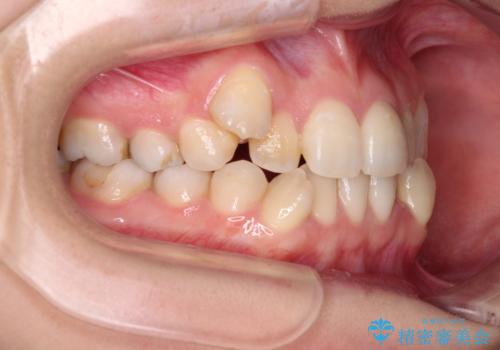

- 上下の八重歯と前歯のデコボコを気にして来院された患者様です。

右上と左下の八重歯が特に著しく、上顎正中が右側にシフトしていました。

デコボコが強いため小臼歯4本を抜歯し、上顎正中を左側に移動させるために補助装置を使用して、ワイヤー装置にて矯正治療を行うこととしました。